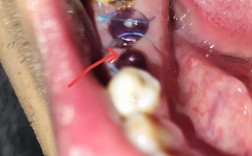

(图片来源网络,侵删)- 原理: 使用牙科高速手机配备不同形状和粗细的金刚石车针(通常是粗颗粒的),在水冷却下,极其精细、轻柔地磨除贴面材料。